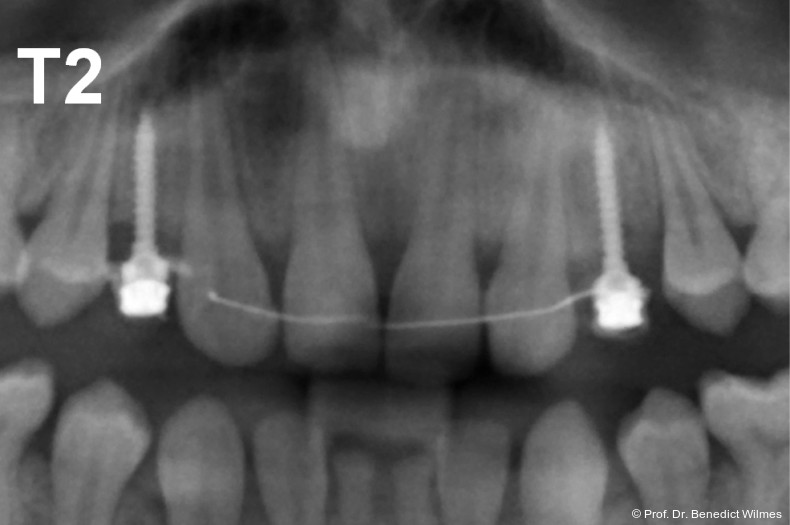

Ein 14-jähriger Patient wurde bei Aplasie der beiden oberen seitlichen Schneidezähne mit dem Ziel der beidseitigen Lückenöffnung kieferorthopädisch therapiert (Abb. 1a+b). Zum Ende der kieferorthopädischen Behandlung wurden zwei Miniimplantate in Regio 2er als temporärer Zahnersatz inseriert (Benefit System, PSM, 2 x 13 mm, Abb. 2a+b). Nach Abdrucknahme wurden Kronen auf den Peek-Abutments modelliert und diese mit Kunststoff auf die Abutments geklebt (Abb. 3a–d). In den Abbildungen 3 und 4 sind die klinischen und röntgenologischen Nachkontrollen innerhalb der nächsten achteinhalb Jahre dokumentiert. Man erkennt einen sowohl in der Höhe als auch in bukkopalatinalen Breite verbleibenden gesunden Knochen ohne Anzeichen einer Atrophie. Im Alter von 23 Jahren wurden die definitiven Implantate ohne die Notwendigkeit einer Augmentation eingesetzt (Abb. 5) und nach Einheilung prothetisch versorgt (Abb. 6a–e und Abb. 7a–c).